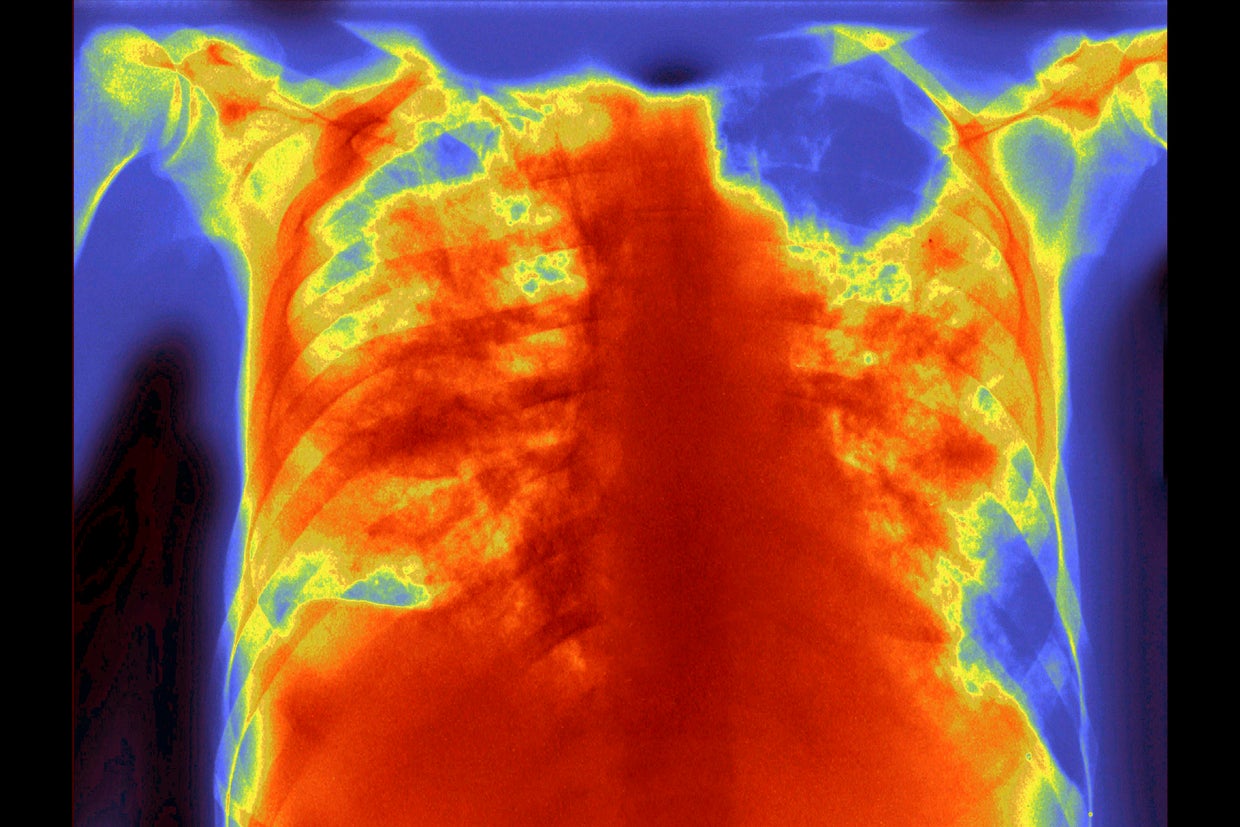

17. Invasive Aspergillosis

BSIP/Universal Image Group/Getty Images

Mortality rate: 30.22%

This X-ray shows lungs infected with a dangerous fungus called Aspergillus. This infection, which primarily affects people with poor immune systems, is 100% fatal if left untreated.